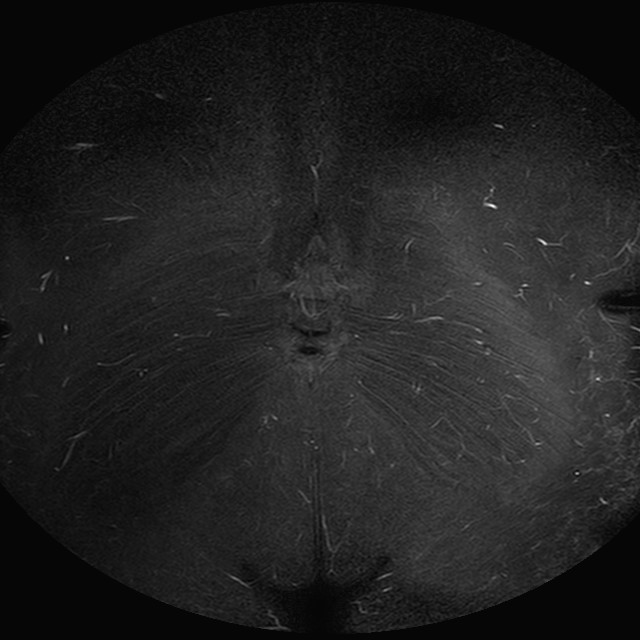

Esami: RMN BACINO

eSTIR

Evidenti e simmetriche alterazioni osteofitosiche in regione coxo femorale con riduzione delle rime articolari. Degenerazione completa del cercine glenoideo. Non attuali segni di versamento articolare. Non segni di edema osseo che escludono attuale algodistrofia od osteonecrosi. Lieve e simmetrica riduzione del trofismo della muscolatura glutea.